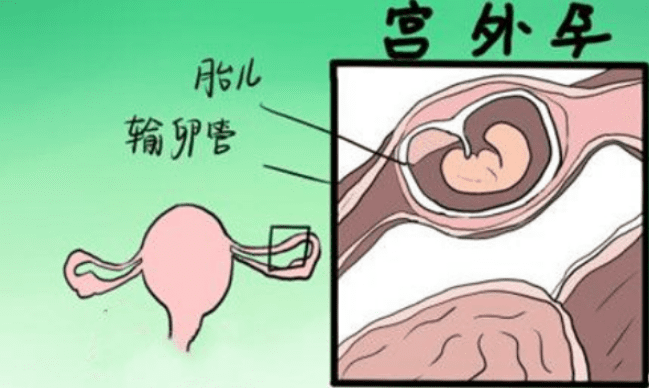

宫外孕是指受精卵在子宫内腔以外着床发育、生长的异常妊娠过程,也称异位妊娠、输卵管妊娠。

什么是宫外孕

正常怀孕受精卵会在子宫内腔着床,但宫外孕顾名思义,是在子宫之外着床。90%以上的宫外孕发生在输卵管,也有少数发生在腹腔、卵巢或宫颈等。